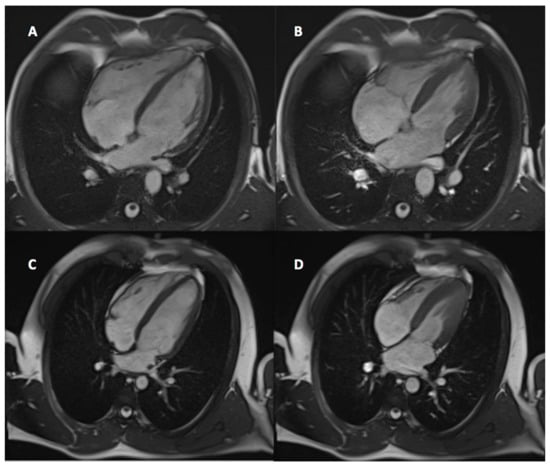

2.3. CMR Protocol and Analysis